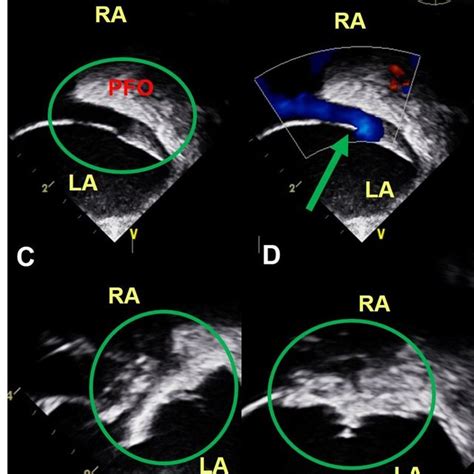

391×391

researchgate.net

| TEE showed a PFO with an ASA (A) and a small amount of left-to-right ...